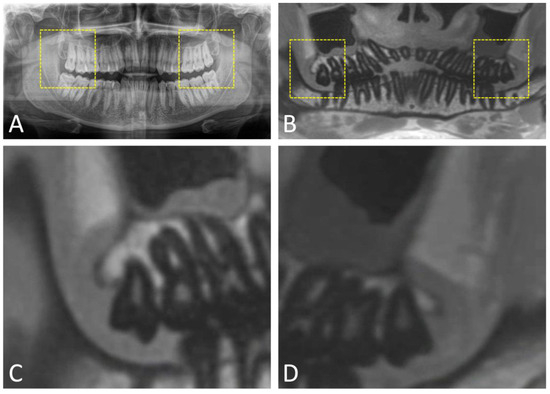

2.1. Orthopantomography (OPG)

2.5. Magnetic Resonance Imaging (MRI)

- Al-Haj Husain, A.; Schmidt, V.; Valdec, S.; Stadlinger, B.; Winklhofer, S.; Schönegg, D.; Sommer, S.; Özcan, M.; Al-Haj Husain, N.; Piccirelli, M. MR-orthopantomography in operative dentistry and oral and maxillofacial surgery: A proof of concept study. Sci. Rep. 2023, 13, 6228. [Google Scholar] [CrossRef] [PubMed]

- Gray, C.F.; Redpath, T.W.; Smith, F.W.; Staff, R.T. Advanced imaging: Magnetic resonance imaging in implant dentistry. Clin. Oral Implants Res. 2003, 14, 18–27. [Google Scholar] [CrossRef] [PubMed]

- Ludwig, U.; Eisenbeiss, A.K.; Scheifele, C.; Nelson, K.; Bock, M.; Hennig, J.; von Elverfeldt, D.; Herdt, O.; Flügge, T.; Hövener, J.B. Dental MRI using wireless intraoral coils. Sci. Rep. 2016, 6, 23301. [Google Scholar] [CrossRef] [PubMed]

- Prager, M.; Heiland, S.; Gareis, D.; Hilgenfeld, T.; Bendszus, M.; Gaudino, C. Dental MRI using a dedicated RF-coil at 3 Tesla. J. Craniomaxillofac Surg. 2015, 43, 2175–2182. [Google Scholar] [CrossRef]

- Al-Haj Husain, A.; Sekerci, E.; Schönegg, D.; Bosshard, F.A.; Stadlinger, B.; Winklhofer, S.; Piccirelli, M.; Valdec, S. Dental MRI of Oral Soft-Tissue Tumors-Optimized Use of Black Bone MRI Sequences and a 15-Channel Mandibular Coil. J. Imaging 2022, 8, 146. [Google Scholar] [CrossRef]